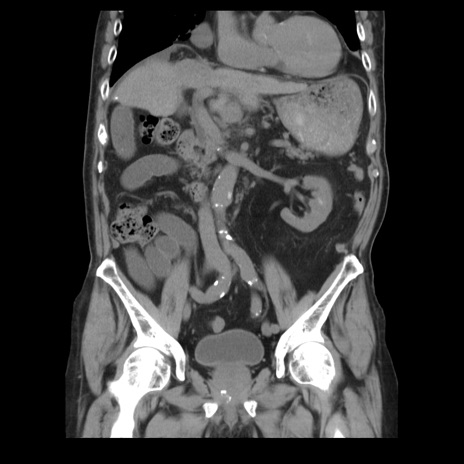

症例21(冠状断像)

【症例】70歳代男性

【主訴】腹痛

【現病歴】肝硬変・肝細胞癌にてかかりつけの方。約9時間前に食後より腹痛出現。症状が徐々に増悪し、嘔吐出現したため来院。

【既往歴】肝硬変、肝細胞癌(RFA、TACE後)

【身体所見】意識清明、表情苦悶様、BT 36℃、BP 129/78mmHg、P 88bpm、SpO2 97%(RA)、右上腹部から心窩部にかけて圧痛あり、反跳痛なし、筋性防御あり。

【データ】WBC 5800、CRP 0.16